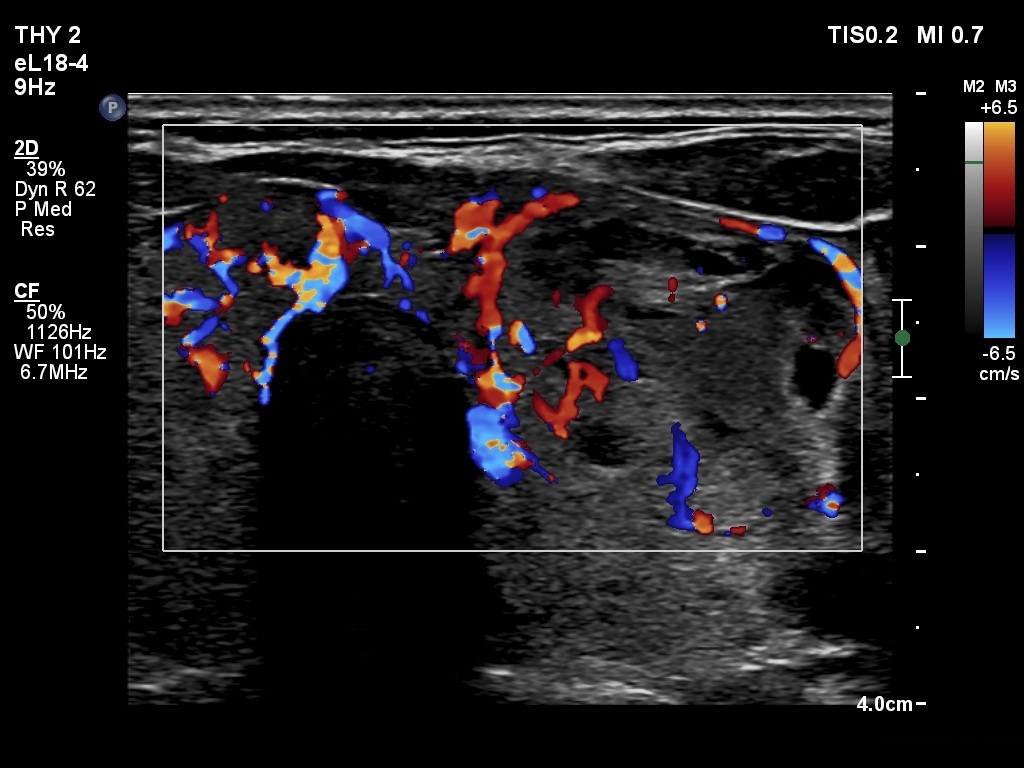

Ultrasonography. The thyroid was echonormal. The right lobe contained several discrete areas without any clinical significance. There was multi-chambered cystic nodule in the left lobe. The nodule had echonormal solid part and presented halo sign.

- The distinction between a multi-chambered cyst and a spongiform cyst is important, because in the latter the risk of malignancy is practically zero. In spongiform cysts almost the entire nodule is composed of cystic areas, and there is very small proportion of solid areas.